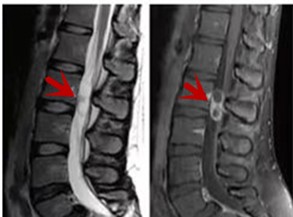

MRI利于磁場和射頻脈沖使體內(nèi)的氫原子核發(fā)生磁共振現(xiàn)象而產(chǎn)生的圖像,對軟組織的分辨率很高,對于脊髓、椎間盤、神經(jīng)、血管、韌帶、骨髓、腰部肌肉及周圍軟組織有很好的顯示效果,可以清晰的顯示腰椎間盤突出對硬膜囊、神經(jīng)根壓迫程度,以及骨折是陳舊還是新鮮,同時(shí)在脊髓病變(如脊髓損傷、髓內(nèi)出血或腫瘤)、椎管內(nèi)膿腫/血腫、椎旁肌肉軟組織病變等方面也具有優(yōu)勢,但是檢查時(shí)間較長,部分患者可能因體內(nèi)金屬植入物(如心臟起搏器、人工耳蝸等)而無法進(jìn)行檢查。

箭頭提示腰椎管內(nèi)腫瘤

紅色箭頭提示新鮮骨折,黃色箭頭提示陳舊性骨折